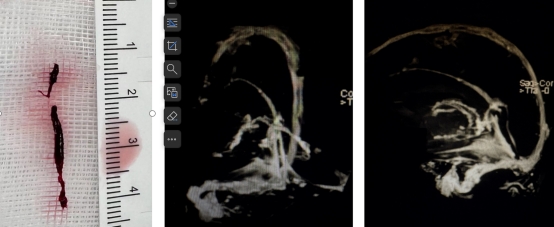

术中血栓及术后复查CE-MRV

术中取出血栓复查MRV正位复查MRV侧位